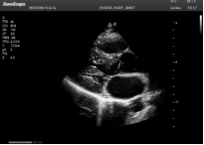

不同的探頭對應(yīng)于不同的臨床領(lǐng)域,不同的探頭頻率也應(yīng)用于不同的人體組織。超聲波在人體中的衰減與探頭頻率有關(guān),探頭頻率越高,穿透力越弱,分辨率越高,而探頭頻率越低,穿透力越強(qiáng),分辨率越低。因此在檢查淺表器官時(shí)應(yīng)選用高頻探頭,而檢查深部臟器時(shí)則選用穿透性強(qiáng)的低頻探頭。